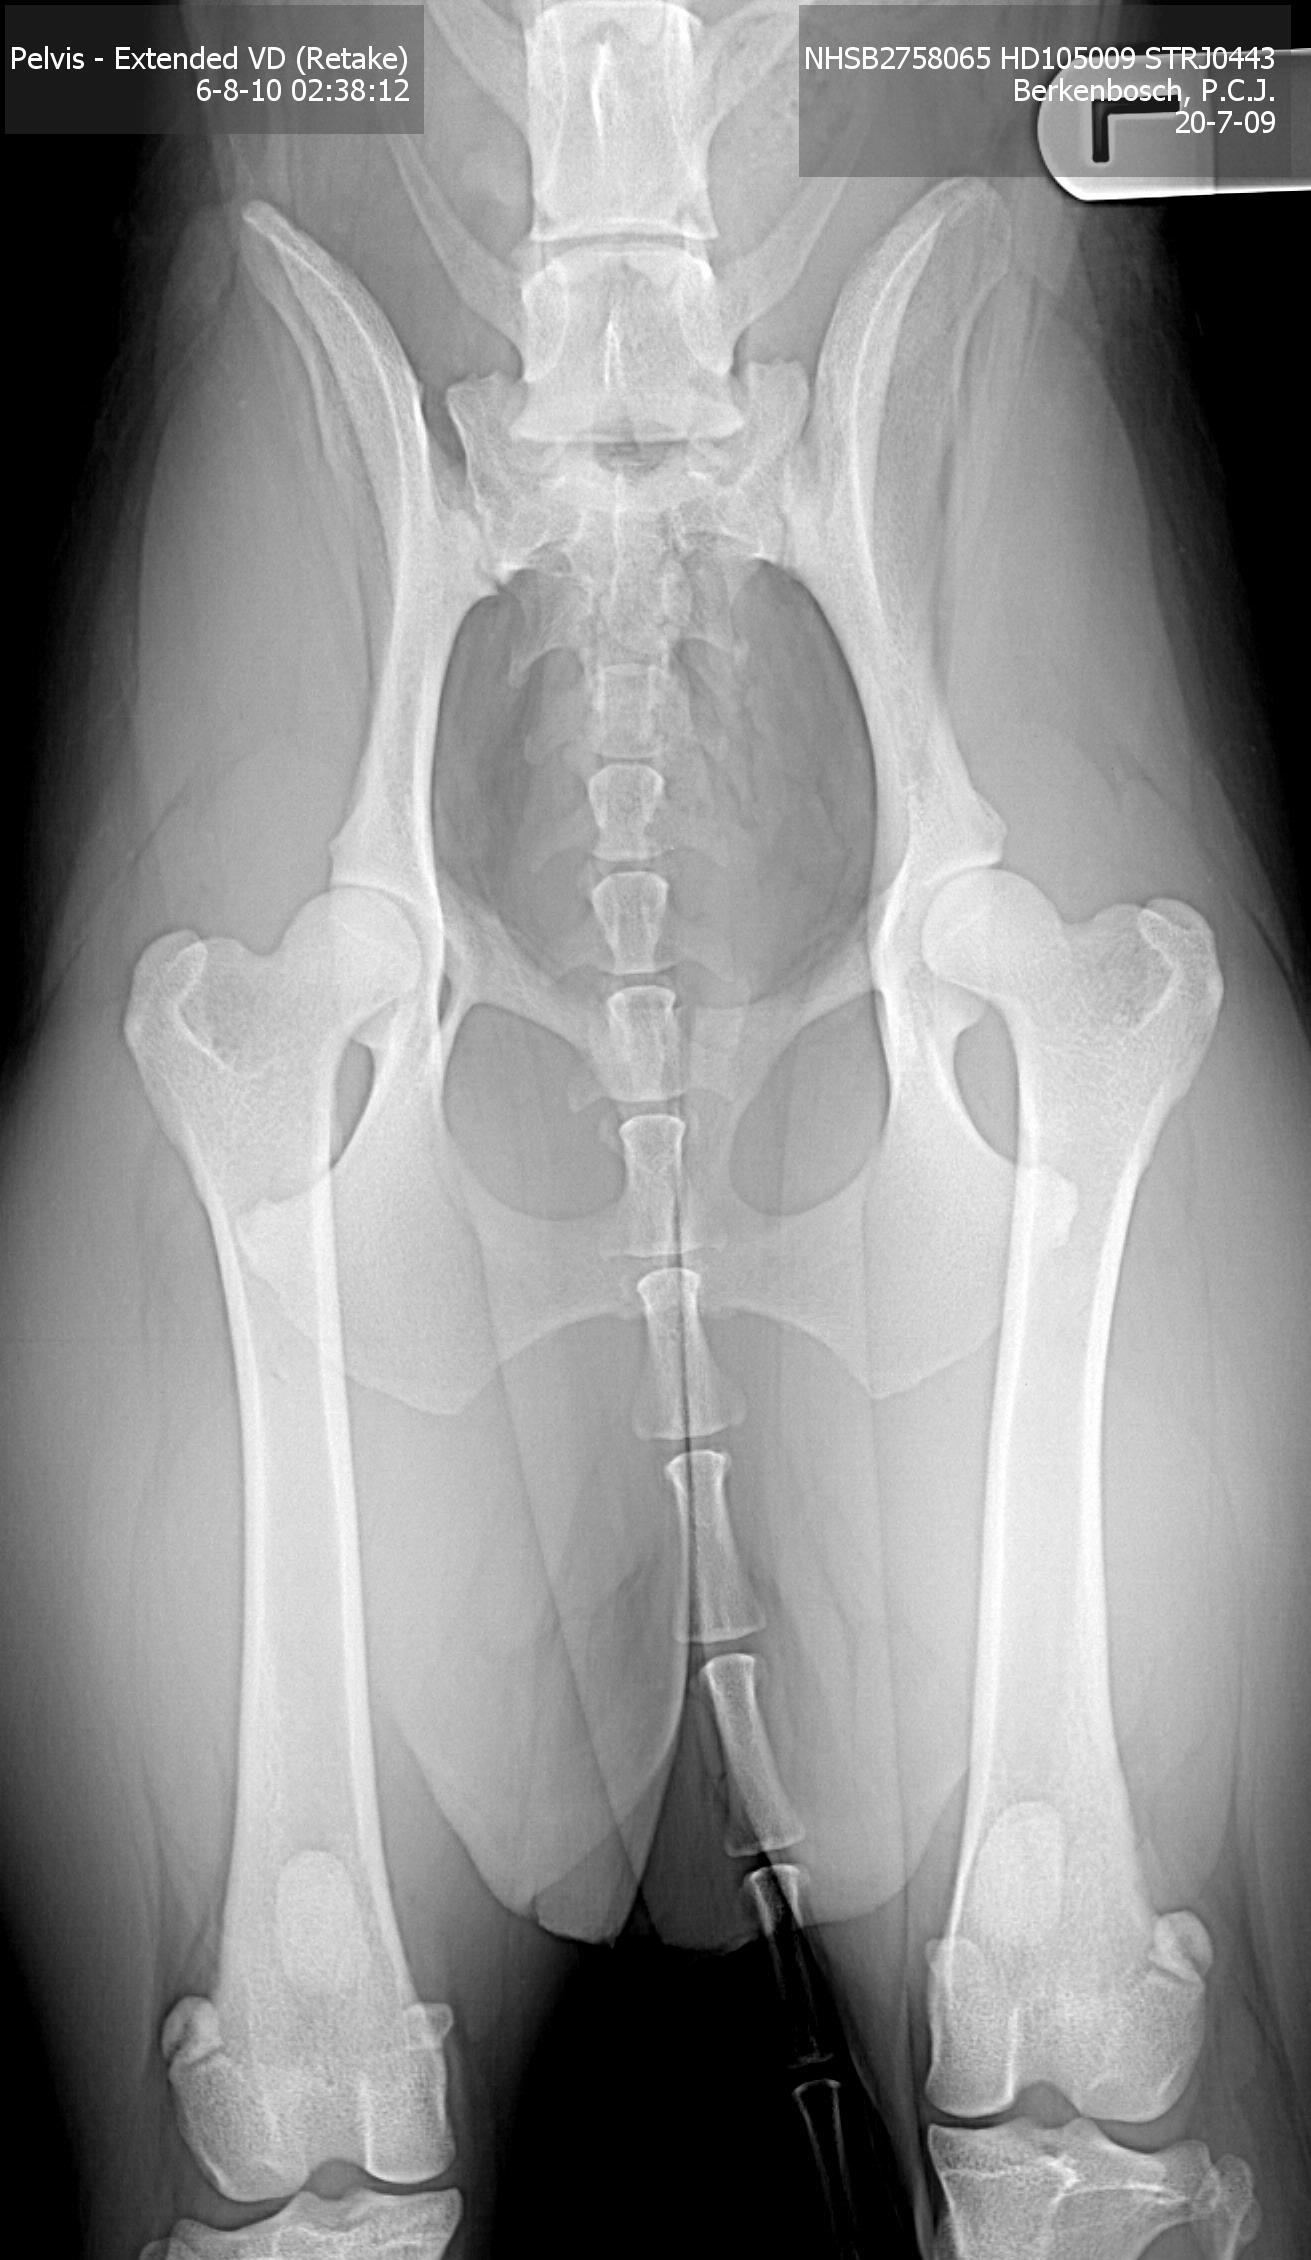

1. Officiële HD-foto

Op 6 augustus 2010 hebben we de officiële HD foto laten maken bij Dierenkliniek Sleeuwijk, door Walter Strikkers.

Hij gaf aan dat ze hele goede heupen heeft. De uitslag van de Raad van Beheer bevestigde dit.

De foto:

Een hele mooie uitslag! We zijn hartstikke blij en dik tevreden!

| Bewegingsapparaat | Heupdysplasie: | Officieel: HD-A |